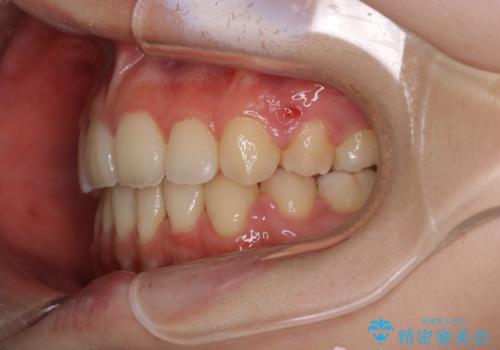

ガタガタも改善しましたが、前歯が内側に引っ込むことにより口元もすっきりして、唇が閉じやすくなりました。